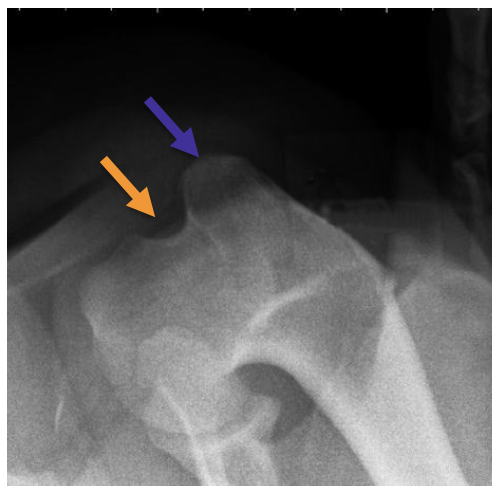

what is the blue arrow pointing to?

greater tubercle of the humerus

what is the orange arrow pointing to?

lesser tubercle of the humerus

what is the groove between the blue and orange arrows called?

intertubercular groove or bicipital groove